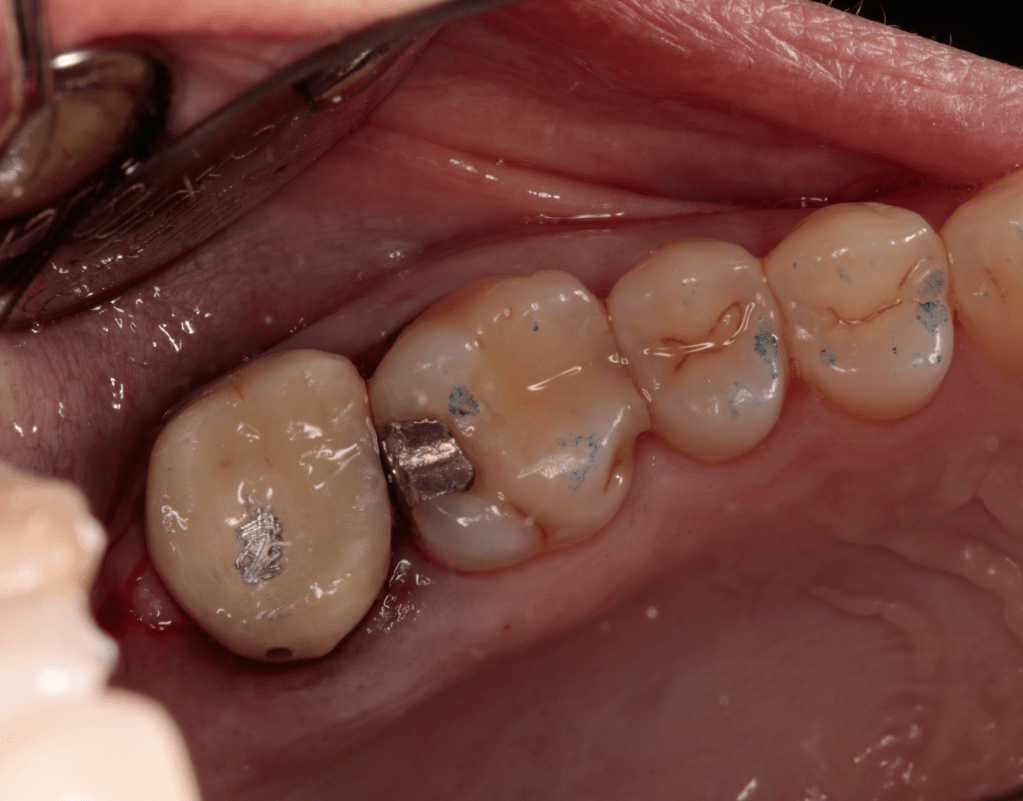

Fisura, remoción amalgama para explorar